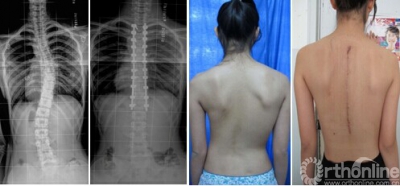

14岁女性患儿,青少年特发性脊柱侧凸,术前术后X线片及外观对比